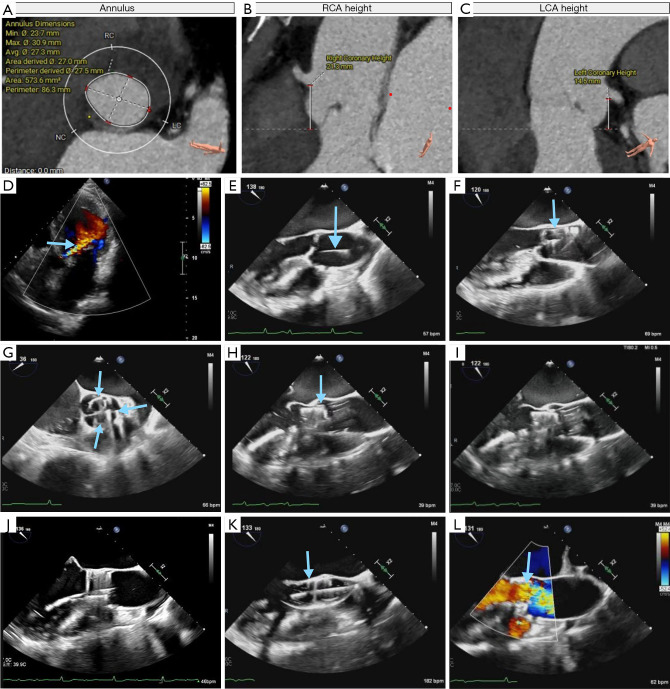

Background: There are few reports about the one-stage surgery of transcatheter aortic valve replacement (TAVR) + mitral valve transcatheter edge-to-edge repair (M-TEER) around the world. TAVR + M-TEER surgery is usually performed under the simultaneous guidance of digital subtraction angiography (DSA) and echocardiography. There is no report of TAVR surgery assisted only by echocardiography all over the world. This case shows a novel one-stage transesophageal echocardiography-guided TAVR + M-TEER surgery, which provides a new idea for minimally invasive therapy.

Case description: A 75-year-old man with recurrent chest tightness was diagnosed with bicuspid aortic valve malformation and severe regurgitation of aortic and mitral valves. The symptom was not relieved by medications. After evaluation with transthoracic echocardiography and computerized tomography angiography (CTA) of the aorta, transapical TAVR and M-TEER were performed simultaneously with satisfied clinical results. The patient's activity tolerance and cardiac function were improved.

Conclusions: In the past, this surgery needs to be performed in a specific operating room equipped with an X-ray machine, and there are many steps in the whole procedure that requires more medical staff. Transesophageal echocardiography-guided minimally invasive valvular surgery reduces the reliance on the hybrid operating room, mitigates the impact of radiation on physicians and patients, and also provides a treatment chance for gravidas with valvular disease.